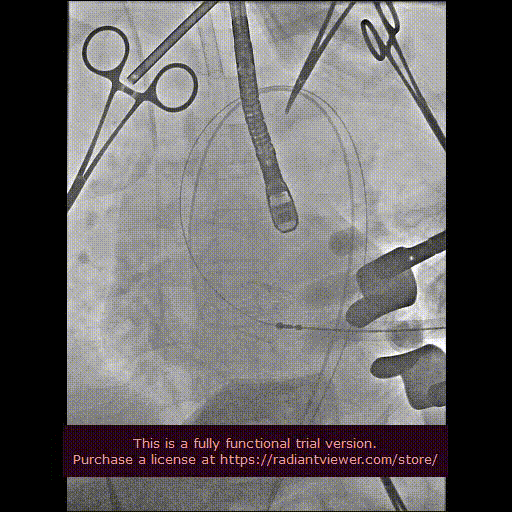

用经胸超声心动图确定心尖位置,并做好标记。常规肝素化,按照心尖标记,行第5、6 肋间左胸前外侧小切口,充分暴露心尖后将心包切开并悬吊,用3-0 Prolene 线加毛毡片完成荷包缝合。经股动脉植入6Fr鞘管,并插入猪尾造影导管至主动脉根部,造影确定主动脉瓣瓣环水平及两侧冠状动脉开口。

经心尖途径置入 J-Valve 瓣膜输送系统,在升主动脉部打开定位件,调整角度,轻轻向后牵拉输送器使定位件进入主动脉窦内。联合主动脉根部造影和食管超声观看定位件是否定位于窦底,形态随着心脏跳动而自然摆动即可。下降瓣膜至主动脉瓣环内,在主动脉瓣口释放瓣膜支架,此过程无需快速起搏。瓣膜成功释放后移除瓣膜输送系统。行主动脉根部造影及经食管超声检查,对瓣膜功能、位置情况进行术后即刻评估。确认位置良好、功能正常后,移除导丝及输送系统,并收紧心尖荷包缝线打结固定。

最后再次血管造影确认介入瓣膜位置稳定,活动良好,无瓣周漏,冠状动脉开口无阻塞。

造影显示主动脉窦部

从心尖置入输送系统

定位件入窦

瓣膜降至瓣环平面

释放瓣膜

造影确认瓣膜位置

撤出输送系统

造影确认植入效果